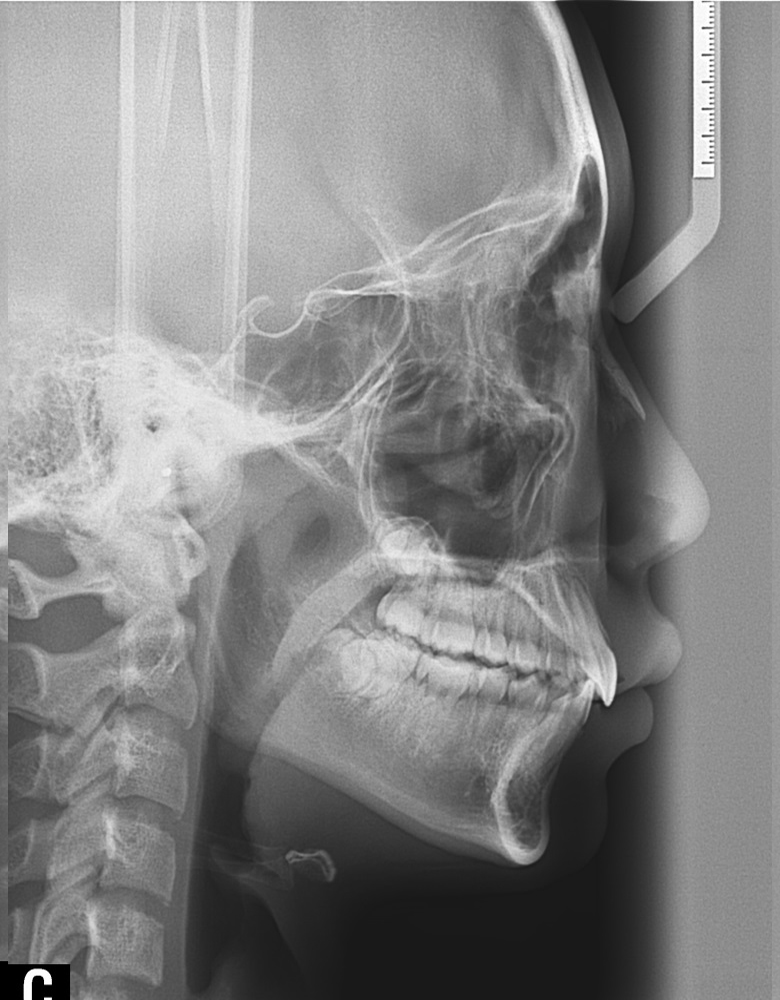

°ú°³±³ÇÕ°ú ¹«ÅÎ,ÅΰüÀýÀ» ÁÖ¼Ò·Î ³»¿øÇÏ¿© ÅμºÀå ¾ÇÁ¤ÇüÀåÄ¡¸¦ ÀÌ¿ëÇÏ¿© Ä¡·áÁßÀΠȯÀÚ·Î Ä¡·á½ÃÀÛ½ÃÁ¡ ±âÁØÀ¸·Î ÇöÀç ۰¡ ¾à 8cmÁ¤µµ ¼ºÀåÇÏ¿´½À´Ï´Ù. (Âü°í·Î 2³âÂ÷ ¿©µ¿»ý°ú ۰¡ 7-9cmŰ Â÷À̳²)